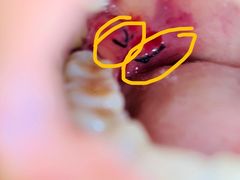

• -华中科技大学同济医学院附属同济医院(汉口院区)

匿名用户 | 21-07-04

报错